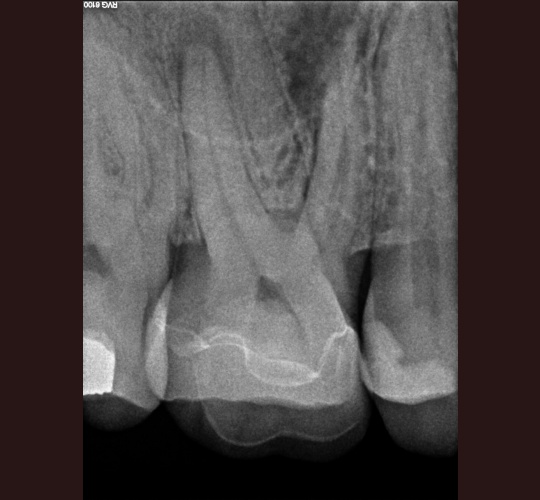

Access Closure: Case #4

When the crown is still intact and in good shape the root canal access opening can be sealed and the crown can be reused. Modern access shape outlines should not overextend and weaken the peri-cervical area. These shapes do not conform to endodontic textbook teachings. These shapes are to be done by qualified microscope using endodontic specialist.

If and only if the doctor feels that sealing your crown can be done to protect your tooth without replacing your crown it may be done in our office by request of your general dentist. If the existing crown is not in excellent shape to prevent leakage into the new root canal your crown may have to be replaced.